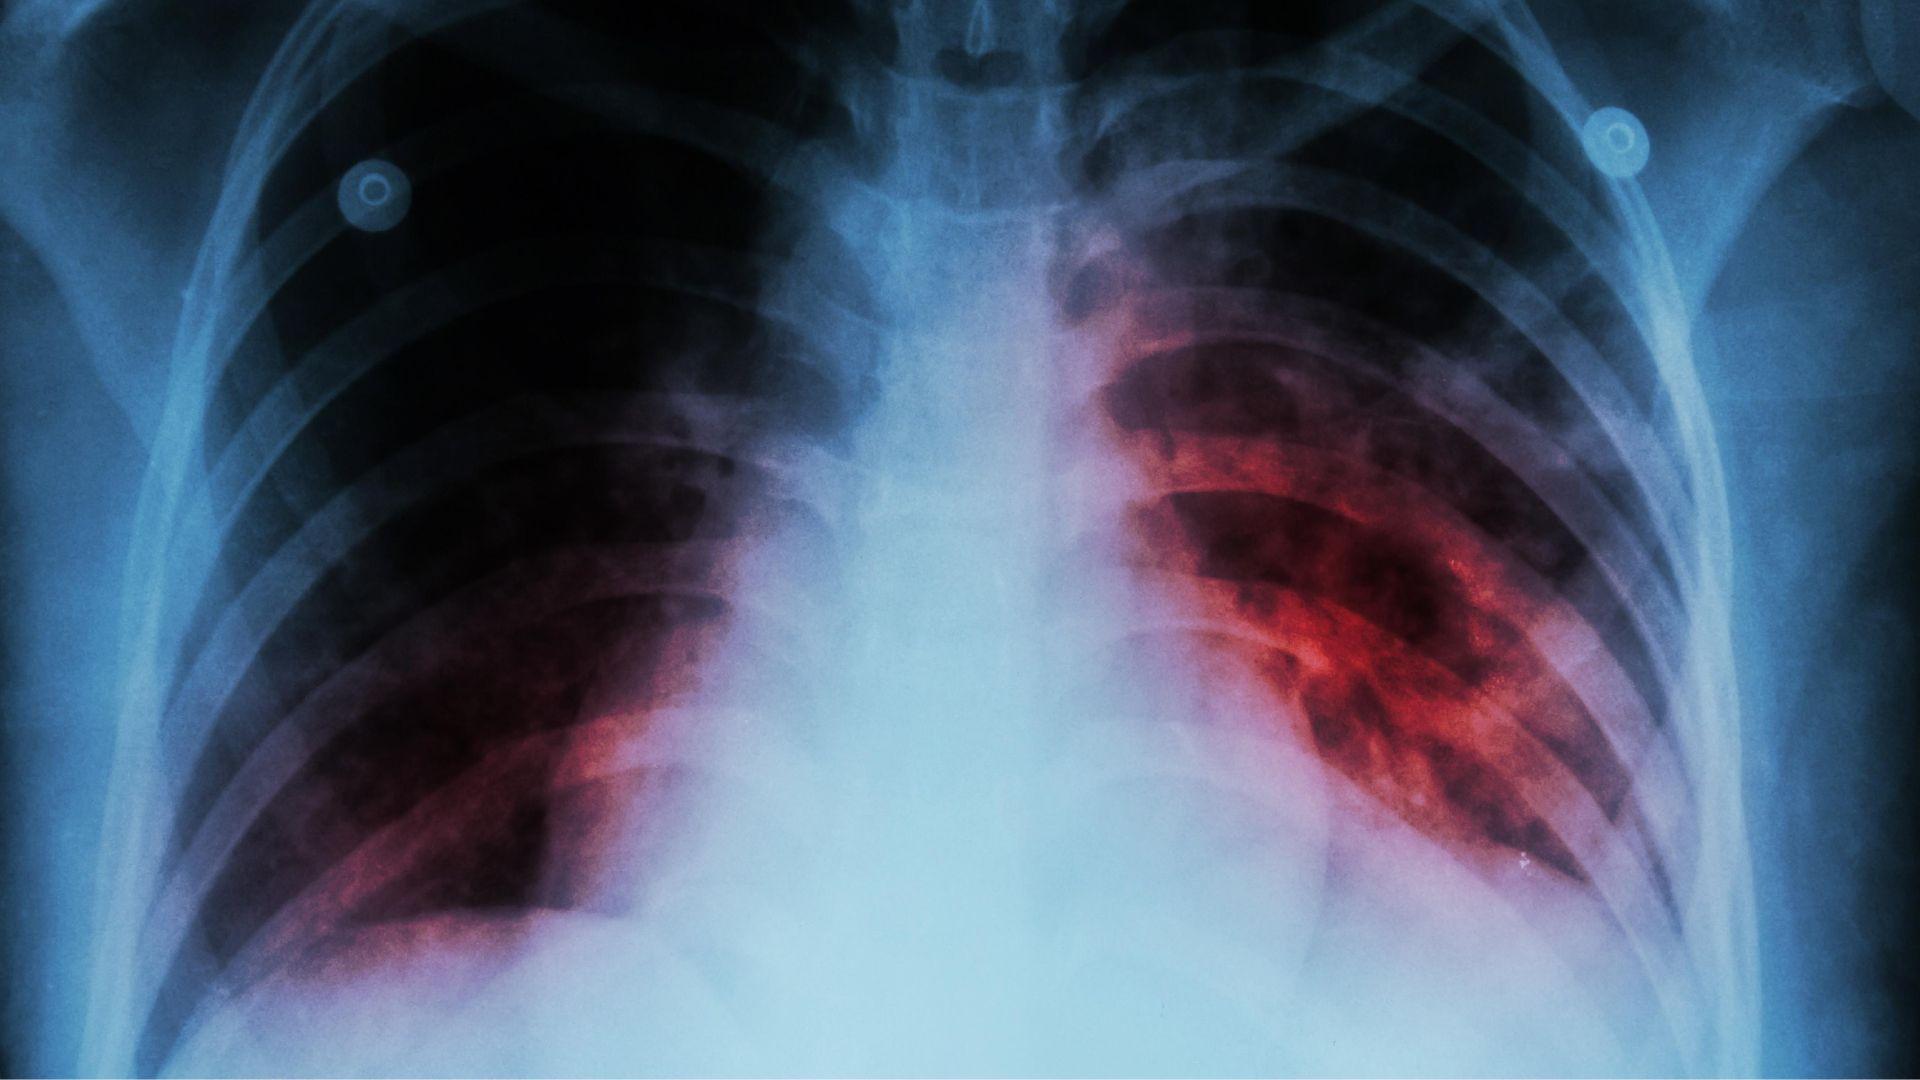

El investigador de El Colegio de la Frontera Sur (Ecosur), y presidente de la Red Mexicana de Investigación en Tuberculosis y Otras Micobacteriosis A.C, Héctor Javier Sánchez Pérez, alertó por el alarmante repunte de casos y muertes por tuberculosis en diferentes regiones de México.

A través de un comunicado, el académico explico que, tras la pandemia de covid-19, la tuberculosis recuperó fuerza y dejó cifras que no se veían desde hace años. El aumento de decesos y la presencia de micobacterias distintas a la tuberculosis son algunos de los signos que más preocupan.

Pérez estima que, solo en México, más de 3,000 personas mueren cada año por esta enfermedad. Cabe señalar que, en el mundo, alrededor de 10 millones de personas se contagian anualmente y más de un millón pierde la vida a causa de este letal agente infeccioso.